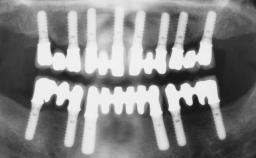

In this video Dr. Legg will demonstrate the process of utilising fully guided surgery as well as reconstruction to provide immediate full arch rehabilitation. A 56-year-old female with chronic adult periodontitis had previously undergone significant nonsurgical periodontal therapy. Unfortunately she had reached the stage where she was no longer happy with the appearance of her teeth and was suffering from increasing discomfort. A full workup was carried out in conjunction with a technical design team (at Createch). This included digital wax up of the proposed teeth, digital placement of the proposed implants and the design of the requisite surgical guides. The surgery was then carried out under sedation. The remaining upper teeth were removed, bone reduced where appropriate and the implants placed using a fully guided protocol. Following placement of screw retained abutments, the immediate provisional prosthesis was picked up in situ and passed to the technician for finishing before being fitted.

Timing of placement Immediate Placement (extraction sockets) (Type I)

Number of implants > Three

Loading Protocol Immediate